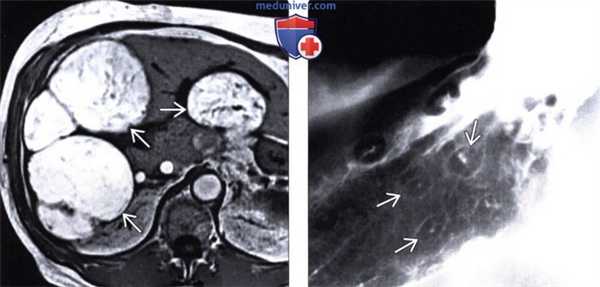

(Слева) На аксиальной МР томограмме (Т1-ВИ) визуализируются множественные метастазы, дающие характерный гипоинтенсивный сигнал на Т1-ВИ, обусловленный высоким содержанием меланина в них. В похожих случаях, метастазы, содержащие жир или кровь, также могут выглядеть гиперинтенсивными на Т1-ВИ.

(Справа) В верхних отделах ЖКТ определяются «классические» поражения в виде «бычьего глаза», представляющие собой мелкие внутристеночные объемные образования с изъязвлением в центре. Лимфома и саркома Капоши также могут проявляться схожими изменениями.